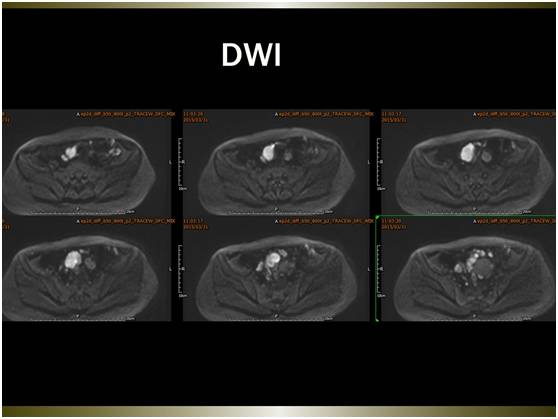

MR平扫及增强示:

大网膜、脏壁腹膜可见弥漫性大小不等略长T1略长T2异常信号,边界不清,FS-T2WI呈高信号,FS-T1WI呈略低信号。注入GD-DTPA后病变明显强化。